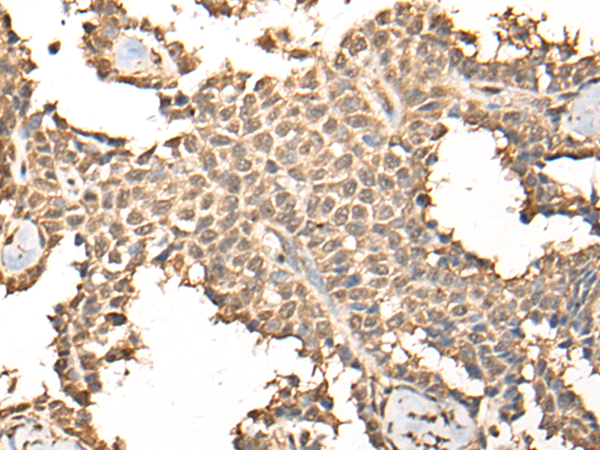

IHC positive control: |

Human ovarian cancer and human thyroid cancer |

ELISA, IHC |